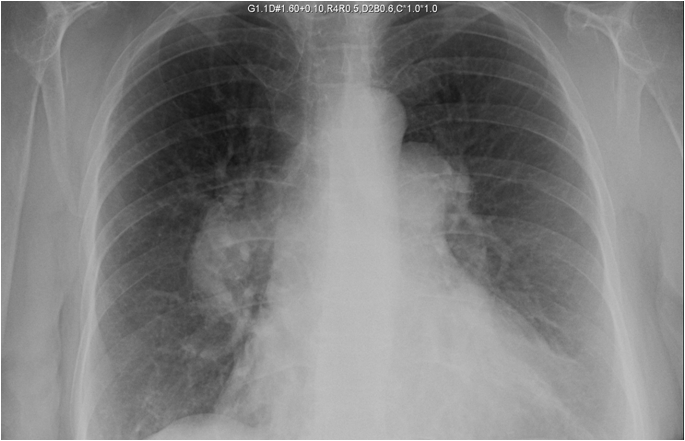

PA and lateral chest radiograph: Large dilated pulmonary arteries bilaterally, cardiomegaly, no active pulmonary disease. (Figure 1)

Figure 1. Posterior-anterior chest radiograph showing massive enlargement of the right and left pulmonary artery.